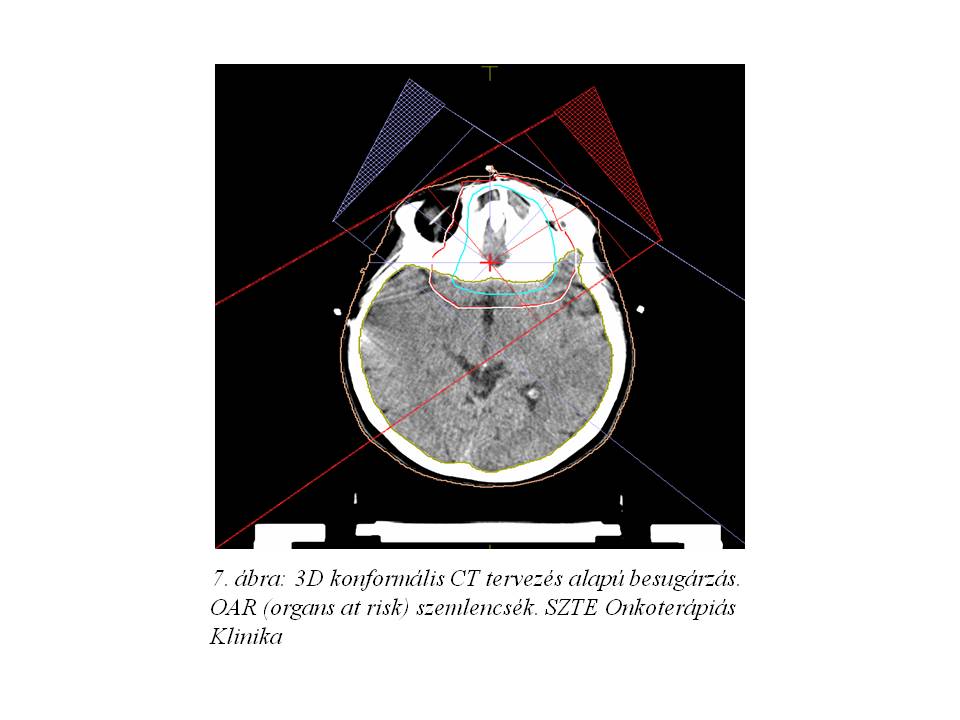

Onkoteam döntés alapján posztoperatív sugárkezelést indítottunk. Betegünk 2015. januártól március elejéig 25x1.8 Gy makroszkópos tumorágy + 6x1.8 Gy boost összdózisú radioterápiában részesült (6. ábra, 7. ábra, 8. ábra). Az agyoedema megelőzése céljából a sugárterápia ideje alatt profilaktikus steroid terápiát alkalmaztunk. A kezelés mellékhatásaként grade I-es radiodermatitis, grade I-es conjunctivitis és részleges alopecia jelentkezett.